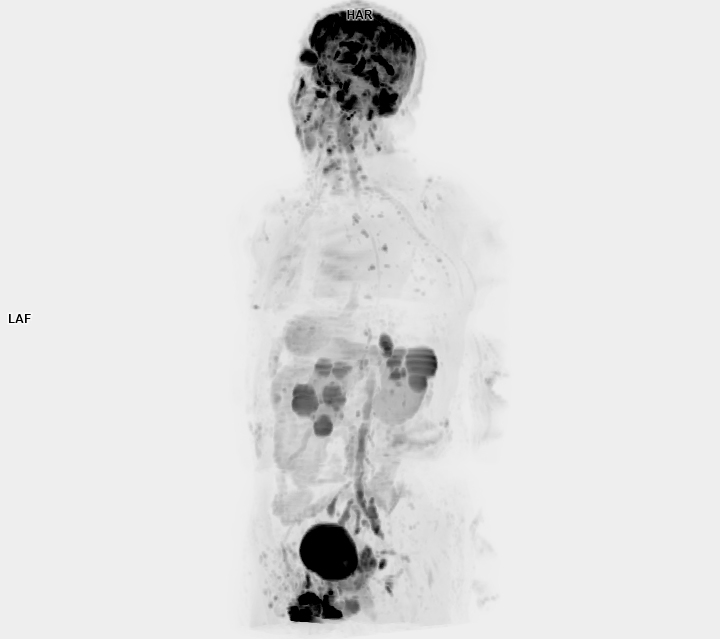

• 3 TESLA MR ÇEKİM GÖRÜNTÜLERİ

3 Tesla MR Çekim Görüntüleri

• 3 Tesla MR Çekim Görüntüleri